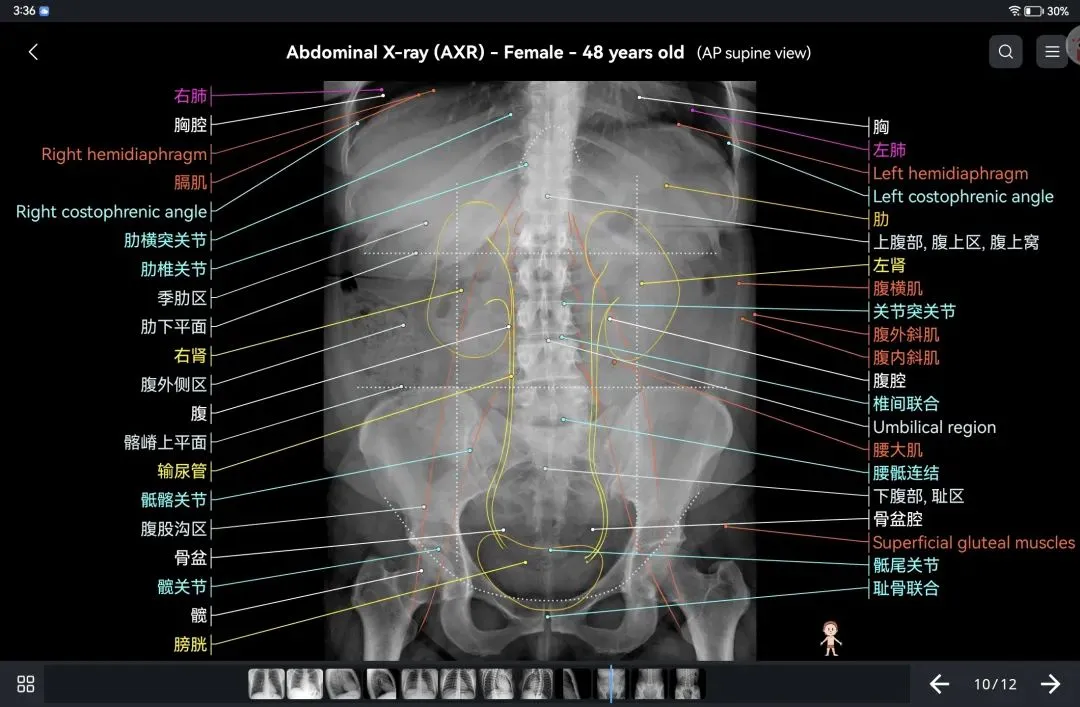

覆盖了X光、CT、MRI、断层大体解剖、核医学、介入造影、医学插图等多个模块,覆盖全身各个系统的影像解剖(正常解剖结构,无病例),其中的解剖结构高达87万个,结构标注超精细,超高清图像,历时两年研发设计完成✅。